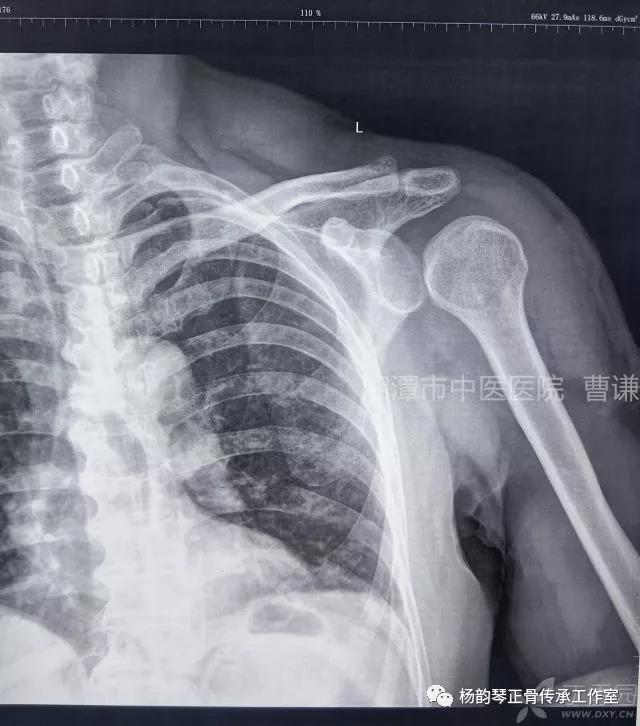

简要病史:骑摩托车跌倒致左肩部肿痛,活动受限,就诊于当地医院,拍片及磁共振检查后诊断为肩袖损伤及肩关节半脱位,予以悬吊固定,因症状缓解不明显就诊于我院。外院拍片情况如下:

应该说是一个典型的“灯泡征”影像,但是并未引起注意。

当地接诊医生应该说还是很负责的,同时拍了健侧片对比:

予以手法复位后拍片复查显示“灯泡征”消失,复位成功。讨论:肩关节后脱位在临床较为少见,特别是影像科经验不足很容易漏报,所以我们临床医生一定要自己仔细阅片,同时要结合体查来进行诊断,防止漏诊。肩关节后脱位时体查也有明显特征:肩关节前方明显变平,喙突较平时明显凸起容易触及,而肩关节后方明显丰满,上臂一般处于内旋内收位,无法主动外旋外展。肩关节后脱位的手法复位相对于前脱位的复位来说也比较容易。患者一般可以取坐位,助手自患侧腋下环抱患者稳定患者躯体,术者一手拉患肢上臂稍牵引内旋,一手自后方推顶肱骨头一般可以复位,如果单纯推顶无法复位也可以术者两手握住伤肢缓慢外展并沿肱骨纵轴牵引,然后逐渐外旋上臂即可复位。整复完成后可以把持患肢作肩关节各个方向的小幅度被动活动,防止肩关节粘连,肩关节后脱位的固定方法与肩关节前脱位的固定方法不同,应将患肢置于上臂外展、后伸、外旋位固定,即外展30度、后伸30度和轻度外旋位,用外展支架固定3周后,循序渐进开始肩关节功能康复。